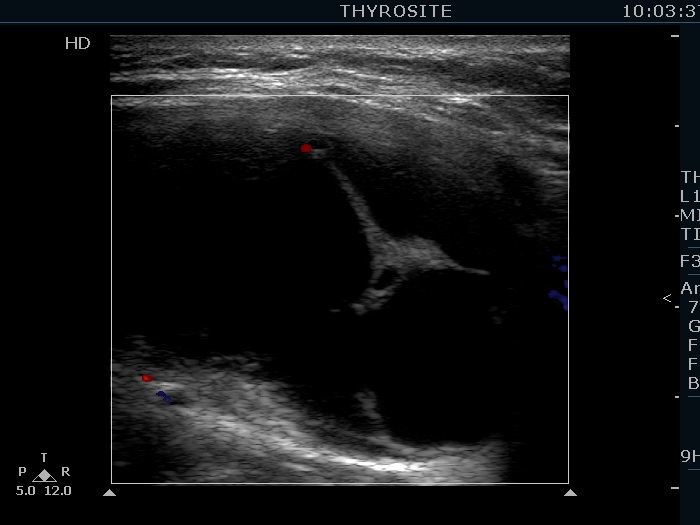

Right lobe, longitudinal scan

Right lobe, longitudinal scan, color Doppler mode. The lesion is avascular.